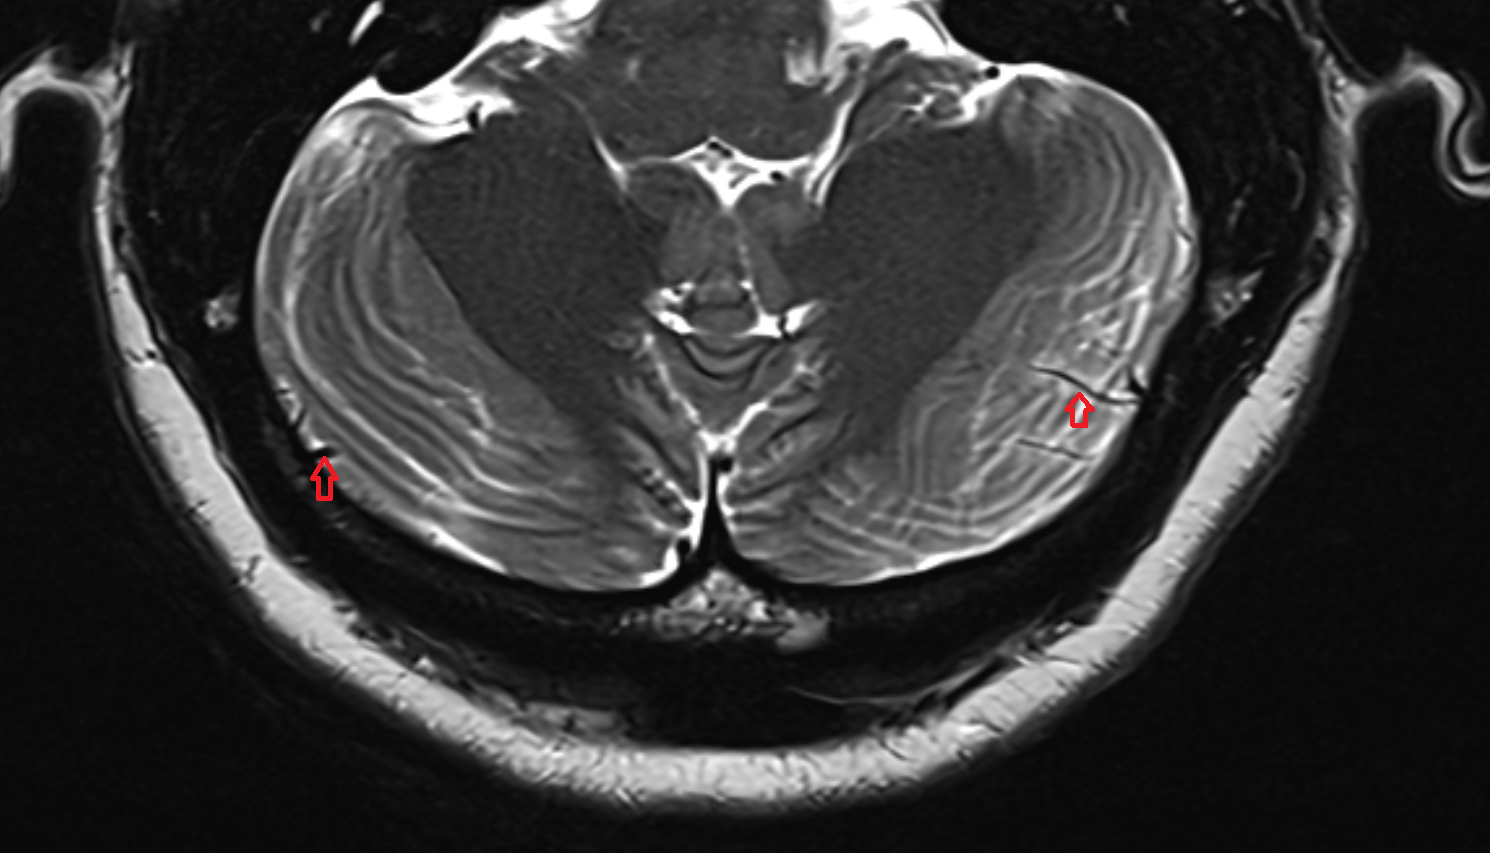

- Cerebellum